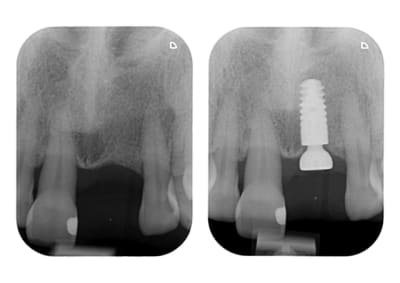

"a pas peur" la 11 ne résistera pas longtemps implant d'entrée de jeux aurait été le mieux il me semble, c'est sur quelque fois le gout bloque le patient mais au vue de la radio chaud chaud les marrons , bon c'est noël c’était facile!!!!!!!!!

Elle est en pleine forme cette 11, pas de mobilité un bel os, je vais essayer de la garder, sinon si ça marche pas, ben on l’enlèvera, en attendant je vais lui laisser sa chance.

Sauf votre respect, il n'y a actuellement aucune papille en mésial de la 11.

Cette dent est parodontalement parlant plutôt môche.

Avec une couronne sur l'implant 21 et une dent 11 tel-quel, ça sera pas beau

L'implant choisi est très bien, connection sous crestal stable.

Il y a amplement d'espace inter-implants pour placer un autre Ankylos et avoir au final quelque chose de bien plus stable que cette dent 11.

Une autre option est égression de la 11, traitement endo et couronne. L'extrusion permettra de créer une lamelle d'os en distal de 11 qui soutiendra la gencive interpapillaire en regard de 21.

Le traitement endo + couronne permet de récupérer un rapport racine dans l'os/ dent hors de l'os plus favorable pour le long terme.

Si le terrain paro est stable ça peut être une bonne option.